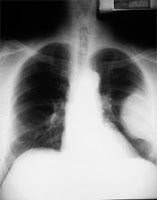

Pleural Mesothelioma

Is the most common form of mesothelioma accounting for roughly 70% of all mesothelioma diagnoses. Pleural mesothelioma begins in the chest cavity and affects the lungs. The most common way for pleural mesothelioma to present itself is through pleural effusion. The initial symptoms that a patient will experience due to the pleural effusion are dyspnea (difficulty breathing), chest pain and/or persistent cough some patients show no symptoms at all. Less common symptoms include fever, night sweats and weight loss.